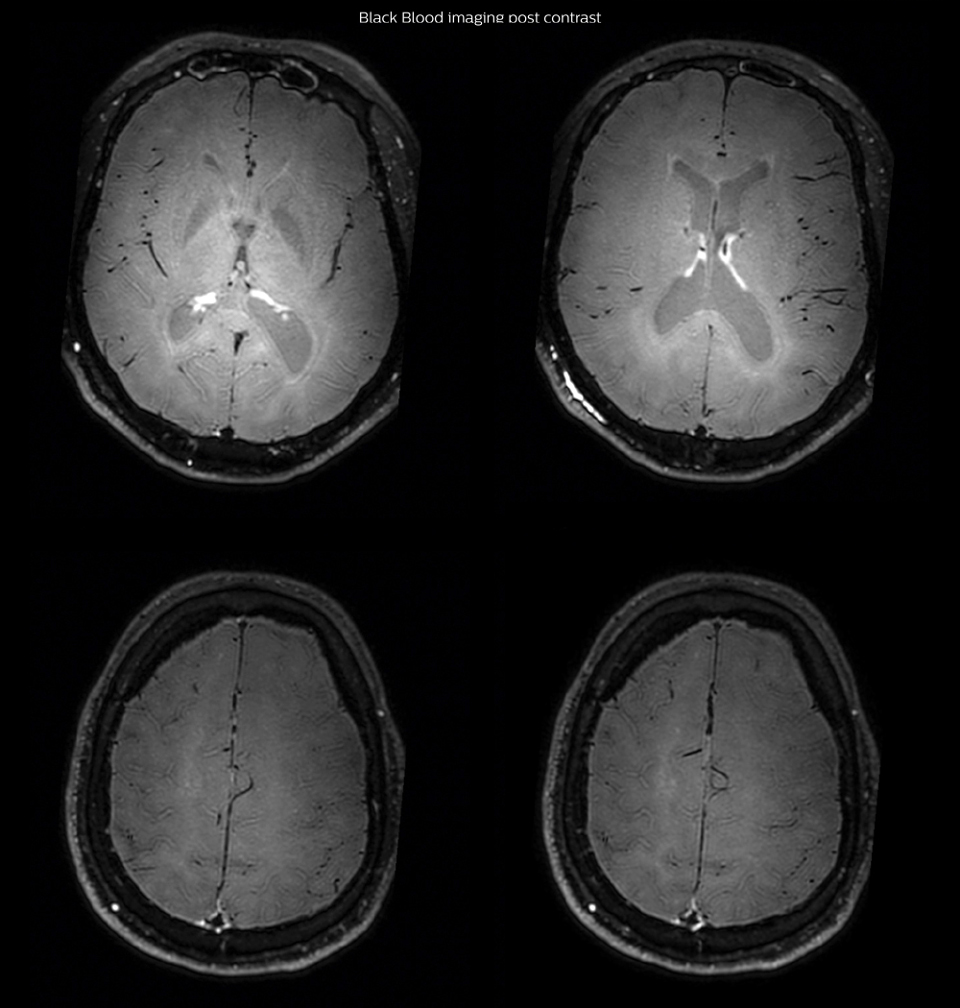

One month after beginning the antiviral treatment, the same

MRI examination was repeated and again 8 months after the

beginning of treatment. On follow-up images, we see the

enhancements have almost disappeared.

So in case of this patient, the MRI exam with Black Blood imaging

helped us to give the patient the appropriate treatment and also

allowed us to noninvasively confirm the treatment response.

Black Blood imaging after one month

After one month of treatment, post-contrast Black Blood images at the exact same levels as in the figure above show disappearance of the vessel wall enhancements which were seen on the previous examination.